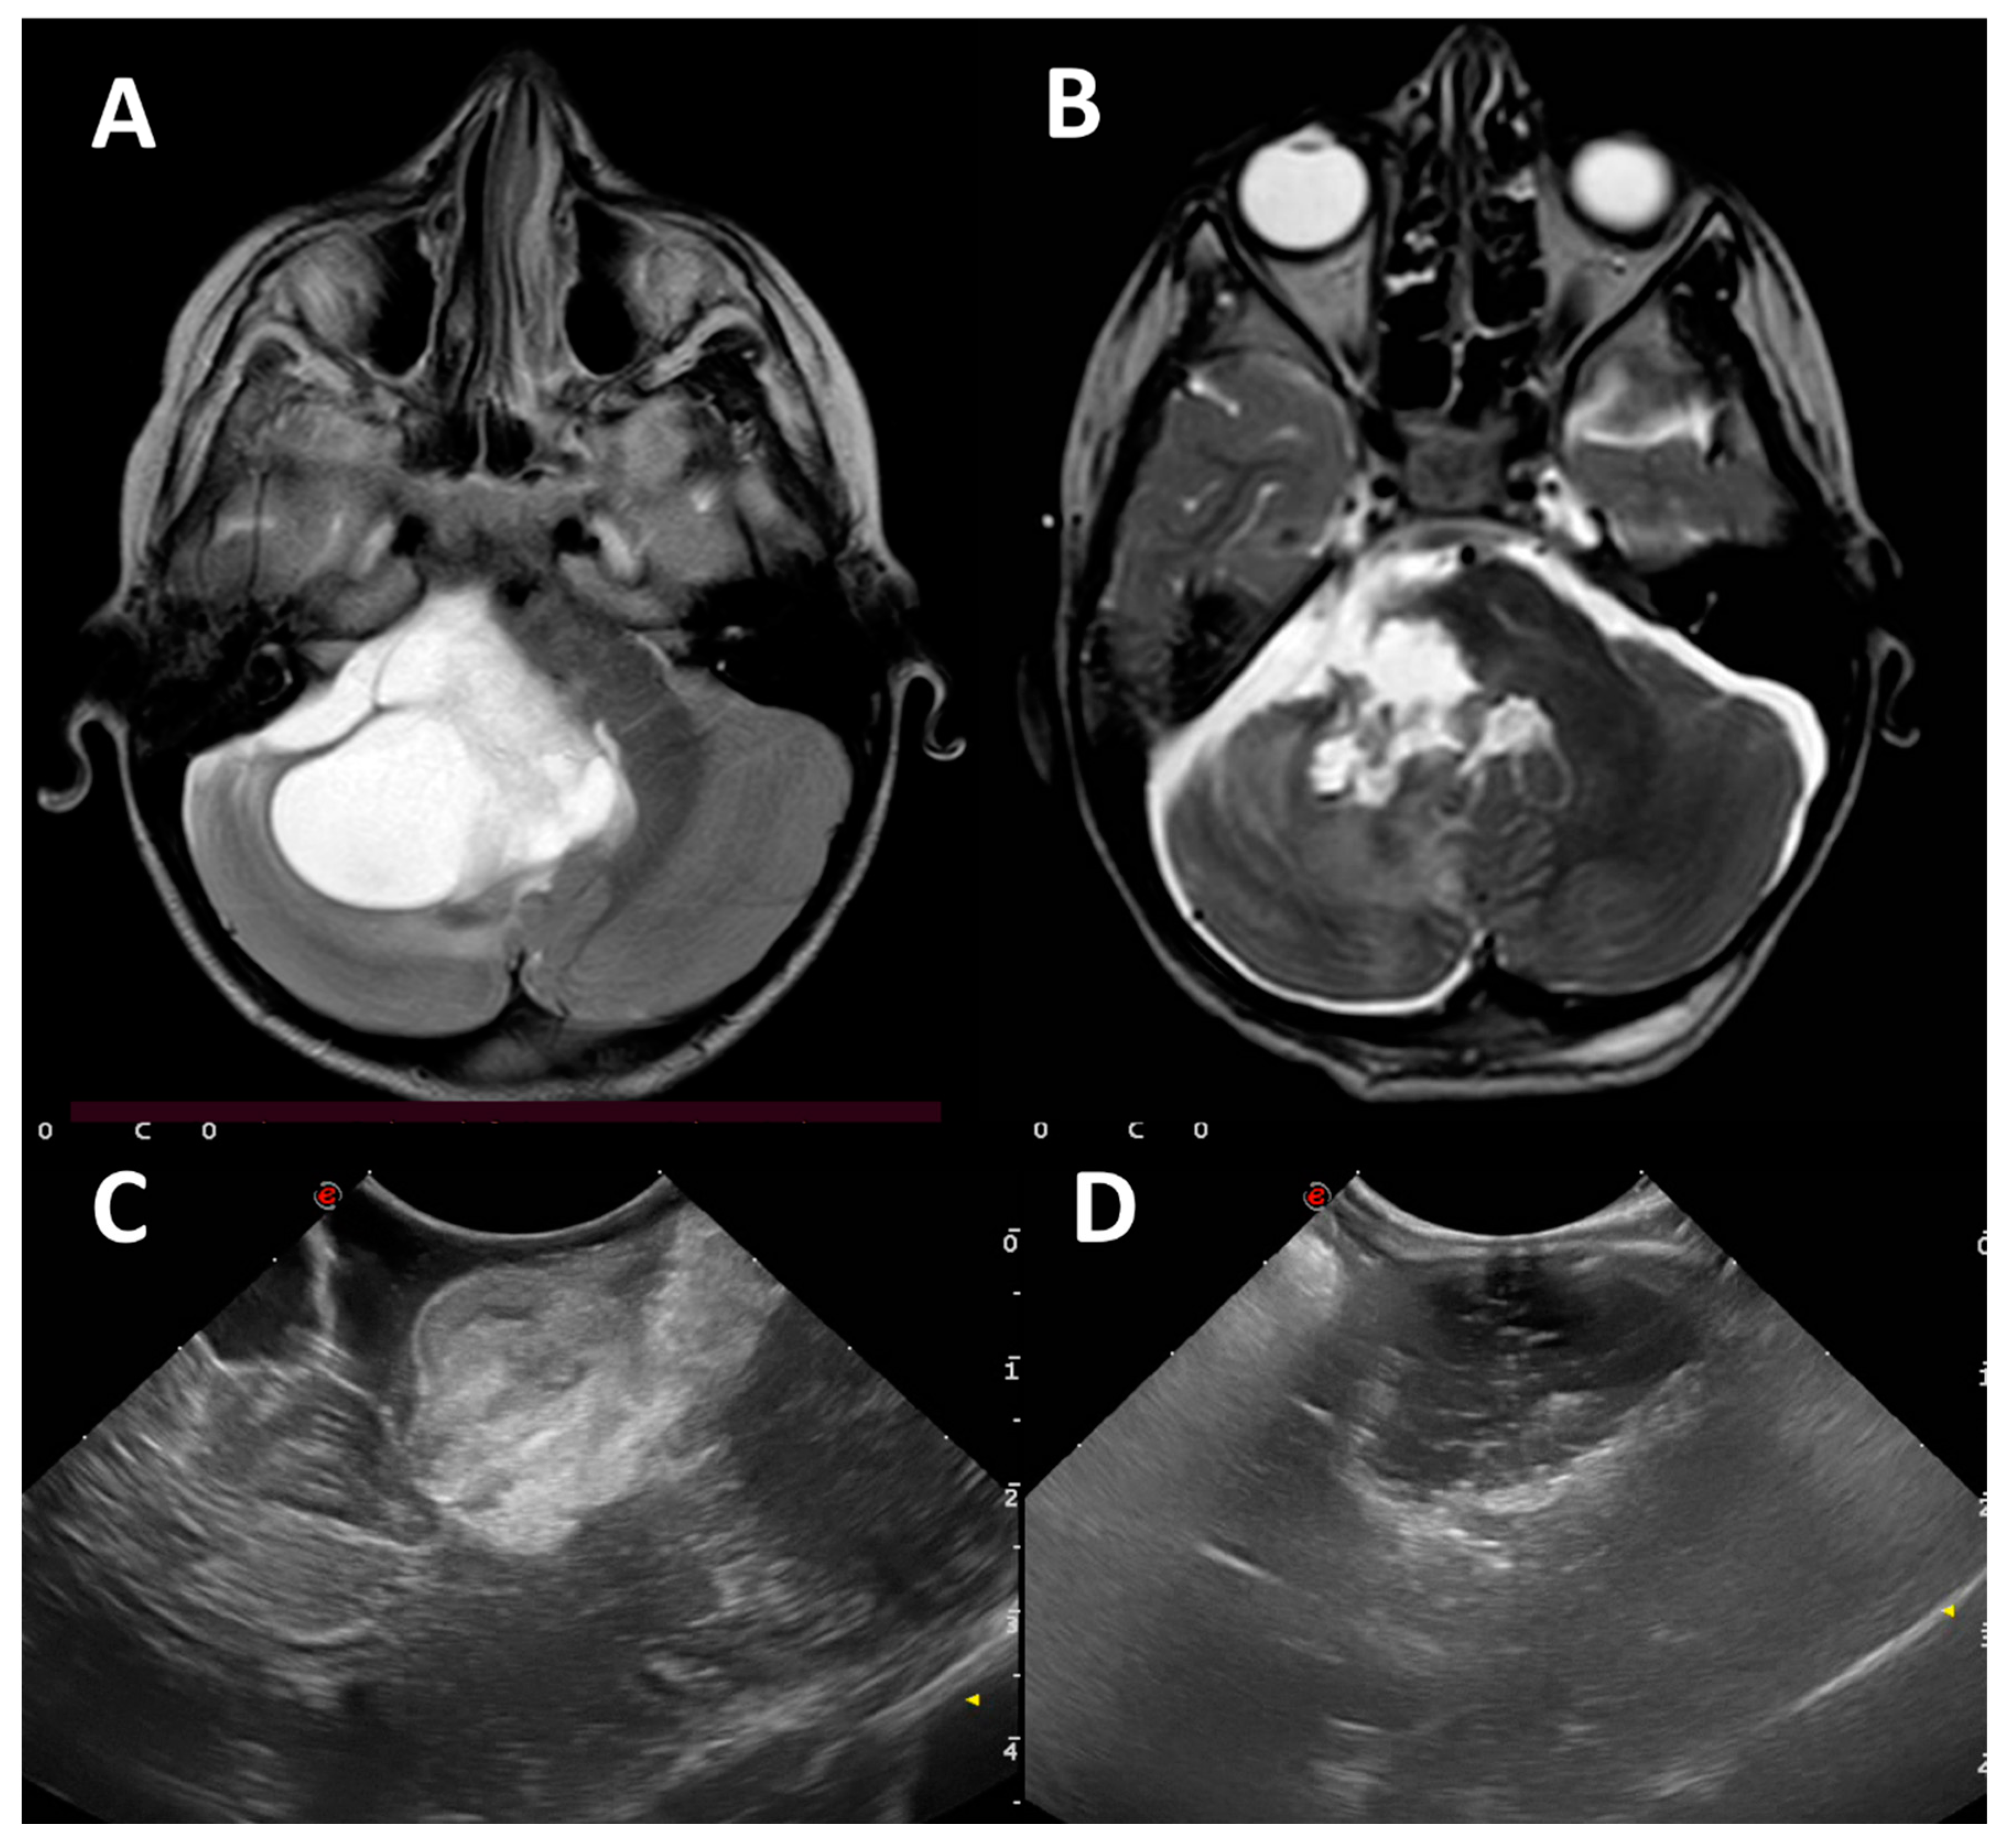

Figure 3. Axial T2 (A) and gadolinium MRI (B) showing of a 4-year-old boy showing a large PF-A ependymoma obstructing the IV ventricle, occupying large part of the posterior fossa and the right CPA. The same sequences (C,D) show a GTR after surgery (realized with exoscope).